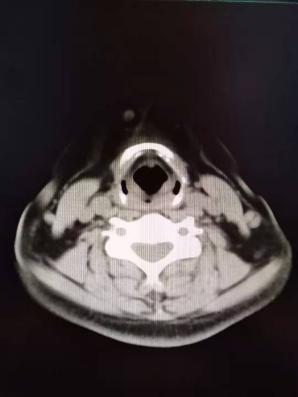

患者的情况不排除是颈部淋巴结转移,于是给患者检查了一个颈部增强CT示:双侧颈部多发淋巴结肿大。患者既往有头晕的症状,且有高血压病史,于是检查了头颅MRI提示:多发性脑梗死。